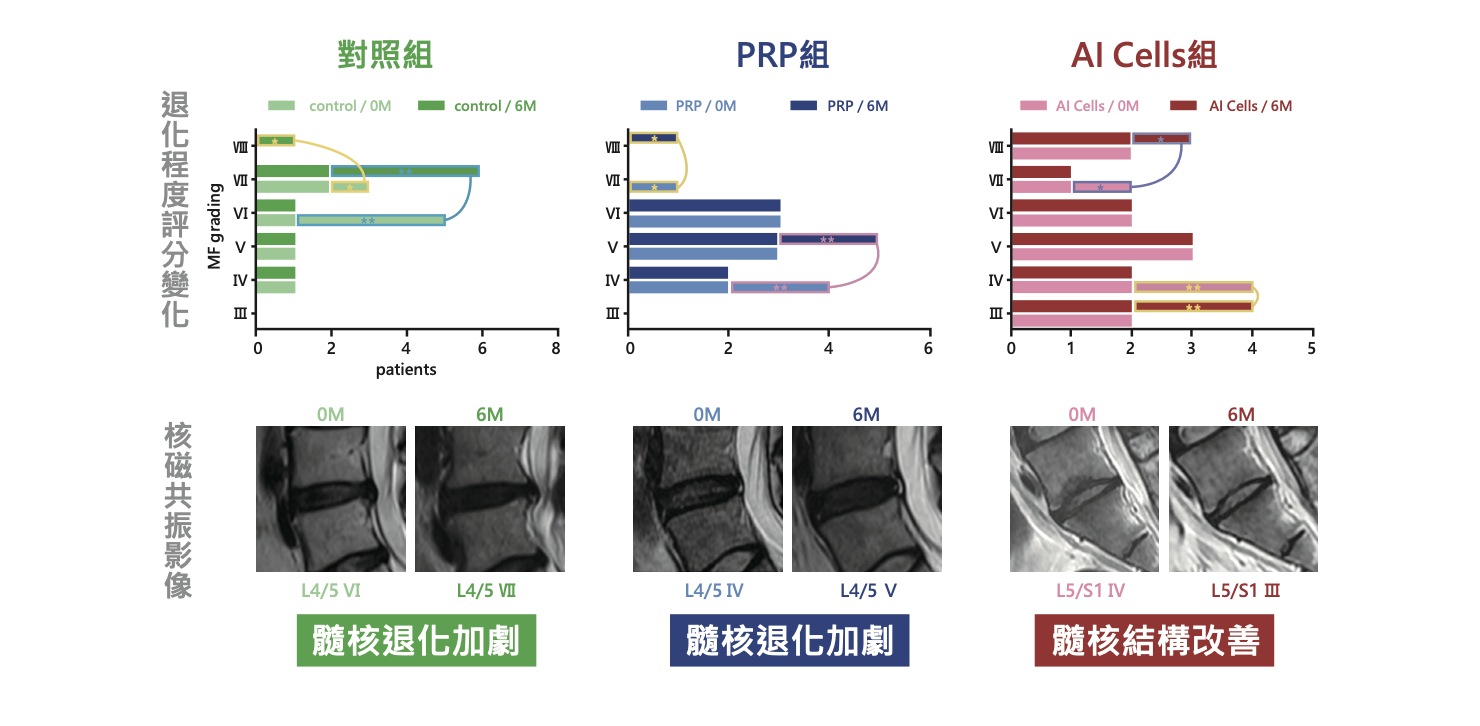

椎間盤退化臨床成果

在椎間盤退化相關資料中,AI Cells 可有效降低椎間盤退化患者的疼痛,改善功能損失並減輕骨水腫。圖中可見疼痛指數(VAS)與失能指數(ODI)於治療後有下降趨勢,同時 MRI 影像也呈現骨水腫改善情況。

另一組比較圖則顯示,相較對照組與 PRP 組,AI Cells 組在維持髓核結構完整性方面表現較佳,對椎間盤退化源性疼痛提供了另一種治療評估方向。